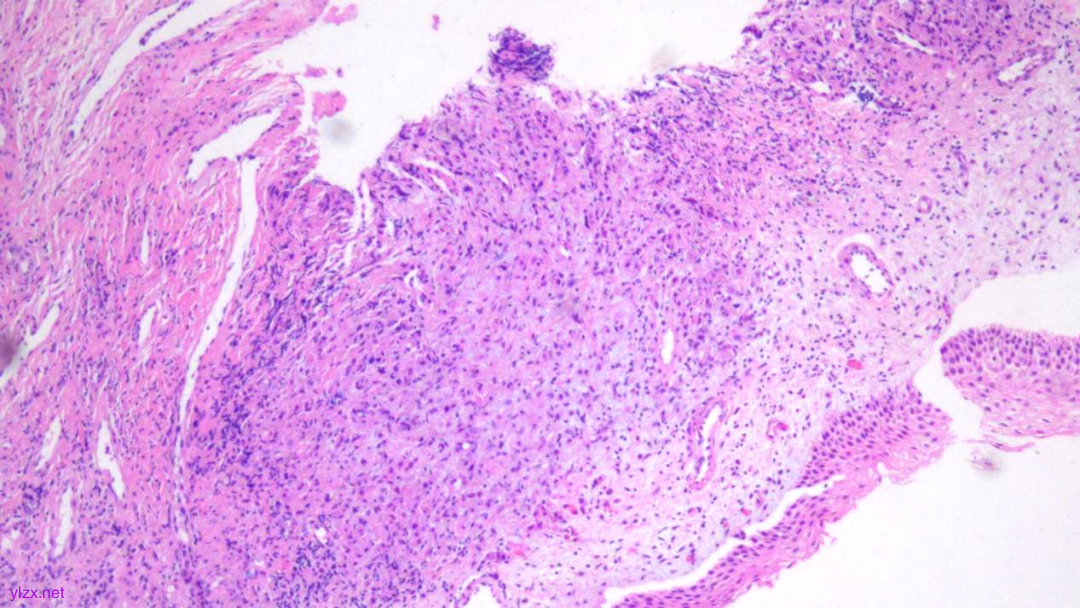

HE:

1.宫颈2点、10点:鳞状上皮下间质内见瘤组织弥漫增生,胞浆宽阔,红染,核小,较一致,部分细胞核偏位,部分细胞可见核仁;

鳞状上皮下间质内见瘤组织弥漫增生,胞浆宽阔、红染,核小,较一致

瘤细胞排列偏稀疏,核小,深染,胞浆红